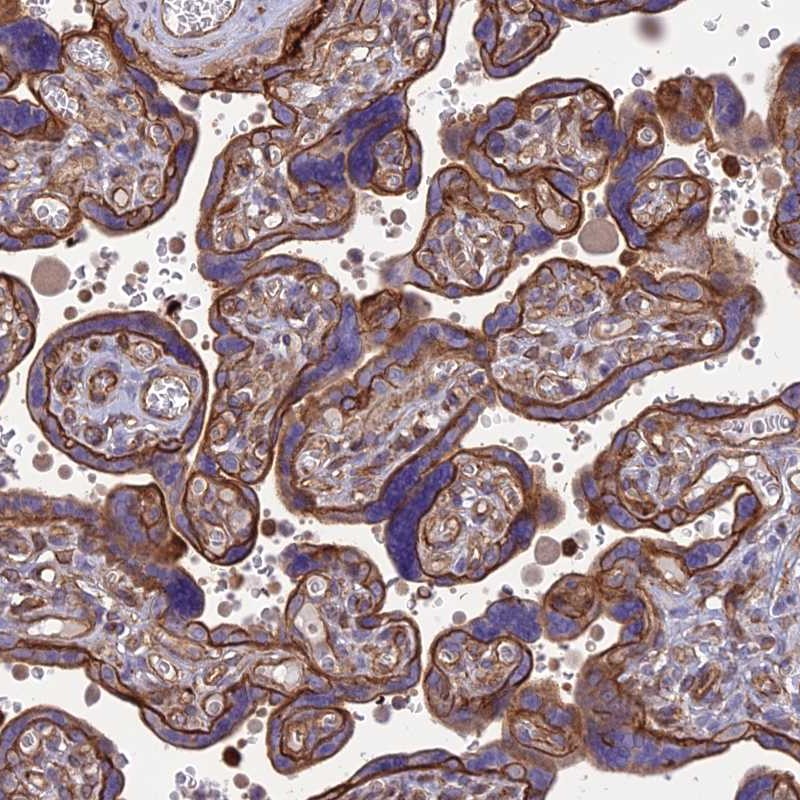

Immunohistochemical staining of human placenta shows strong membranous positivity in trophoblastic cells.